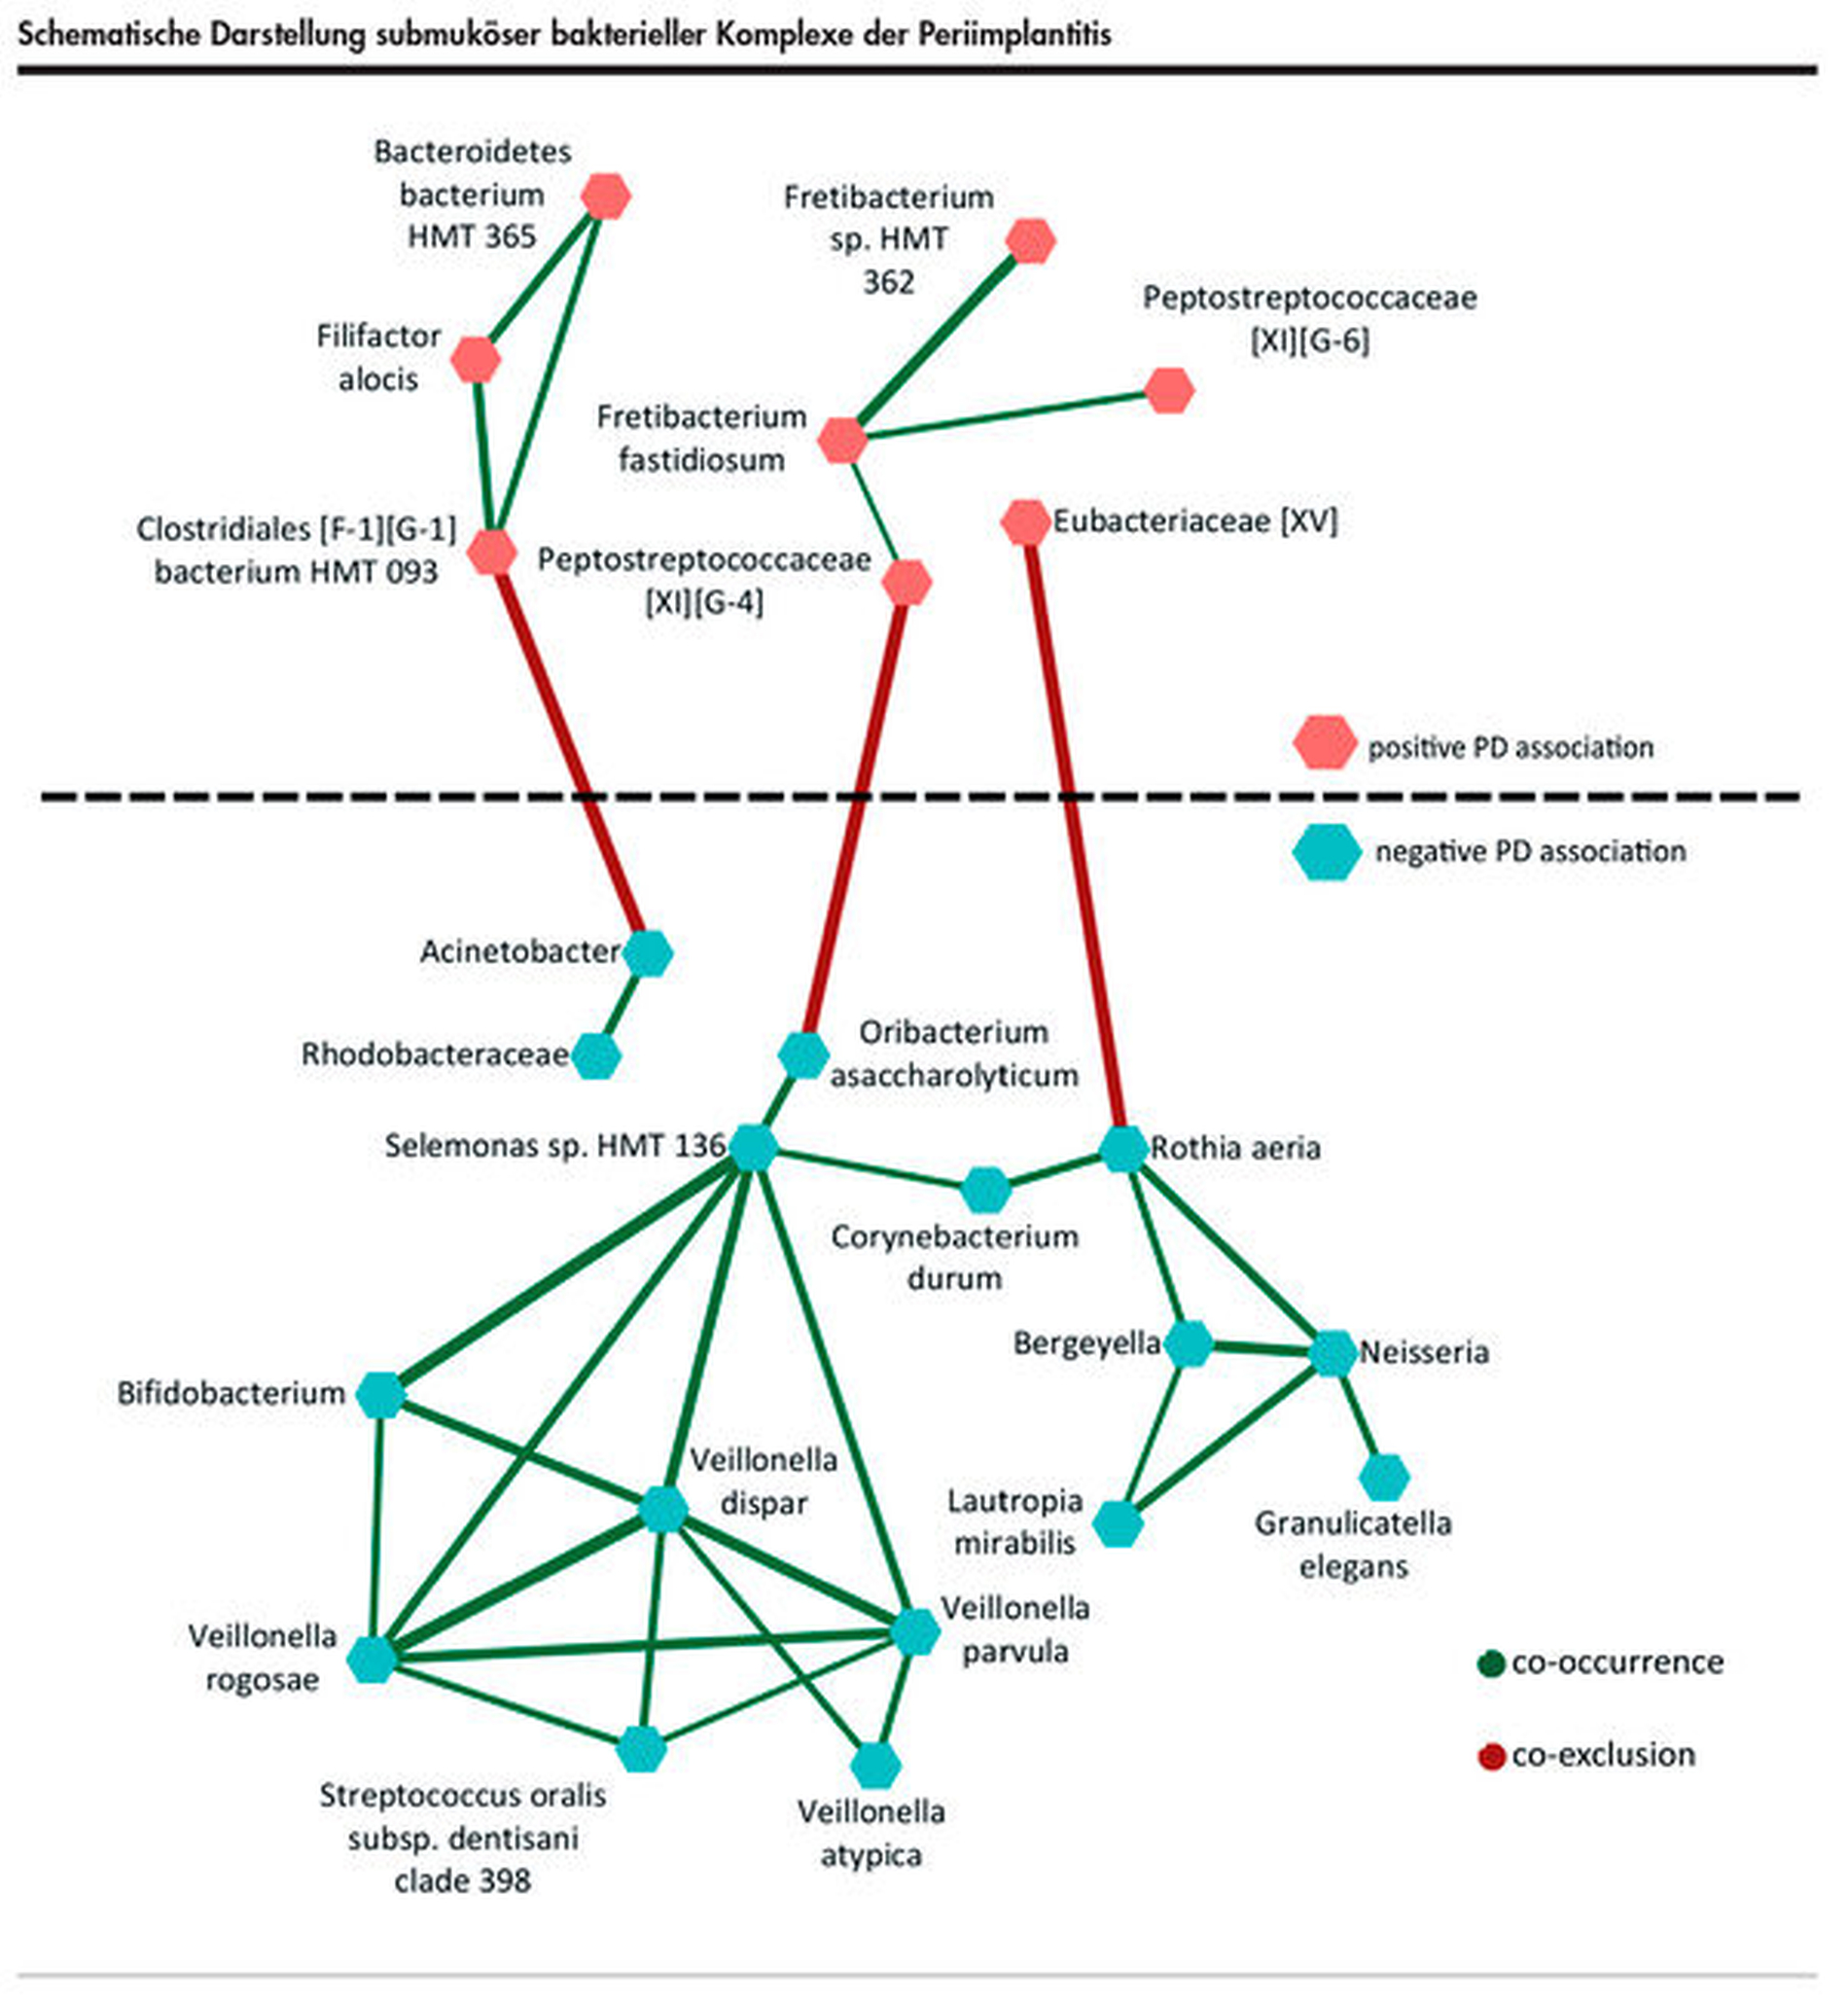

Submuköse Bakterien-Komplexe

Der Begriff der ‚bakteriellen Komplexe‘ wurde durch Socransky et al. bei der Parodontitis geprägt [Socransky et al., 1998]. Dabei können Bakterien dank ihrer symbiotischen und pathogenen Eigenschaften in verschiedene Komplexe zusammengefasst werden, wobei jeder Komplex eine unterschiedliche Virulenz aufweist und in bestimmten Stadien der Parodontitis eine wichtige Rolle spielt. Am bekanntesten ist wohl der ‚rote Komplex‘ – dabei handelt es sich um die höchst parodontalpathogenen anaeroben Keime P. gingivalis, T. forsythia und T. denticola [Socransky et al., 1998].

Auch im Bereich der Periimplantitis gibt es in der aktuellen Literatur Hinweise auf funktionelle bakterielle Komplexe im submukösen Biofilm [Ghensi et al., 2020; Kröger et al., 2018]. Korrelationsanalysen haben dabei mikrobielle Netzwerke aufgezeigt (Abbildung 3). Interessanterweise gruppieren sich dabei solche Spezies zu funktionellen Einheiten, die entweder mit einem erhöhten Schweregrad assoziiert sind oder umgekehrt. Die Komplexe, die aus Bakterien mit positiver Schweregradassoziation bestehen, enthalten häufig Spezies, die in der Vergangenheit bereits mit destruktiven Prozessen in Zusammenhang gebracht wurden. Umgekehrt findet man in den gesundheitsassoziierten Komplexen häufig auch gesundheitsassoziierte Spezies. Darüber hinaus scheint sich die Koexistenz von gesundheits- und destruktionsassoziierten Komplexen auszuschließen.